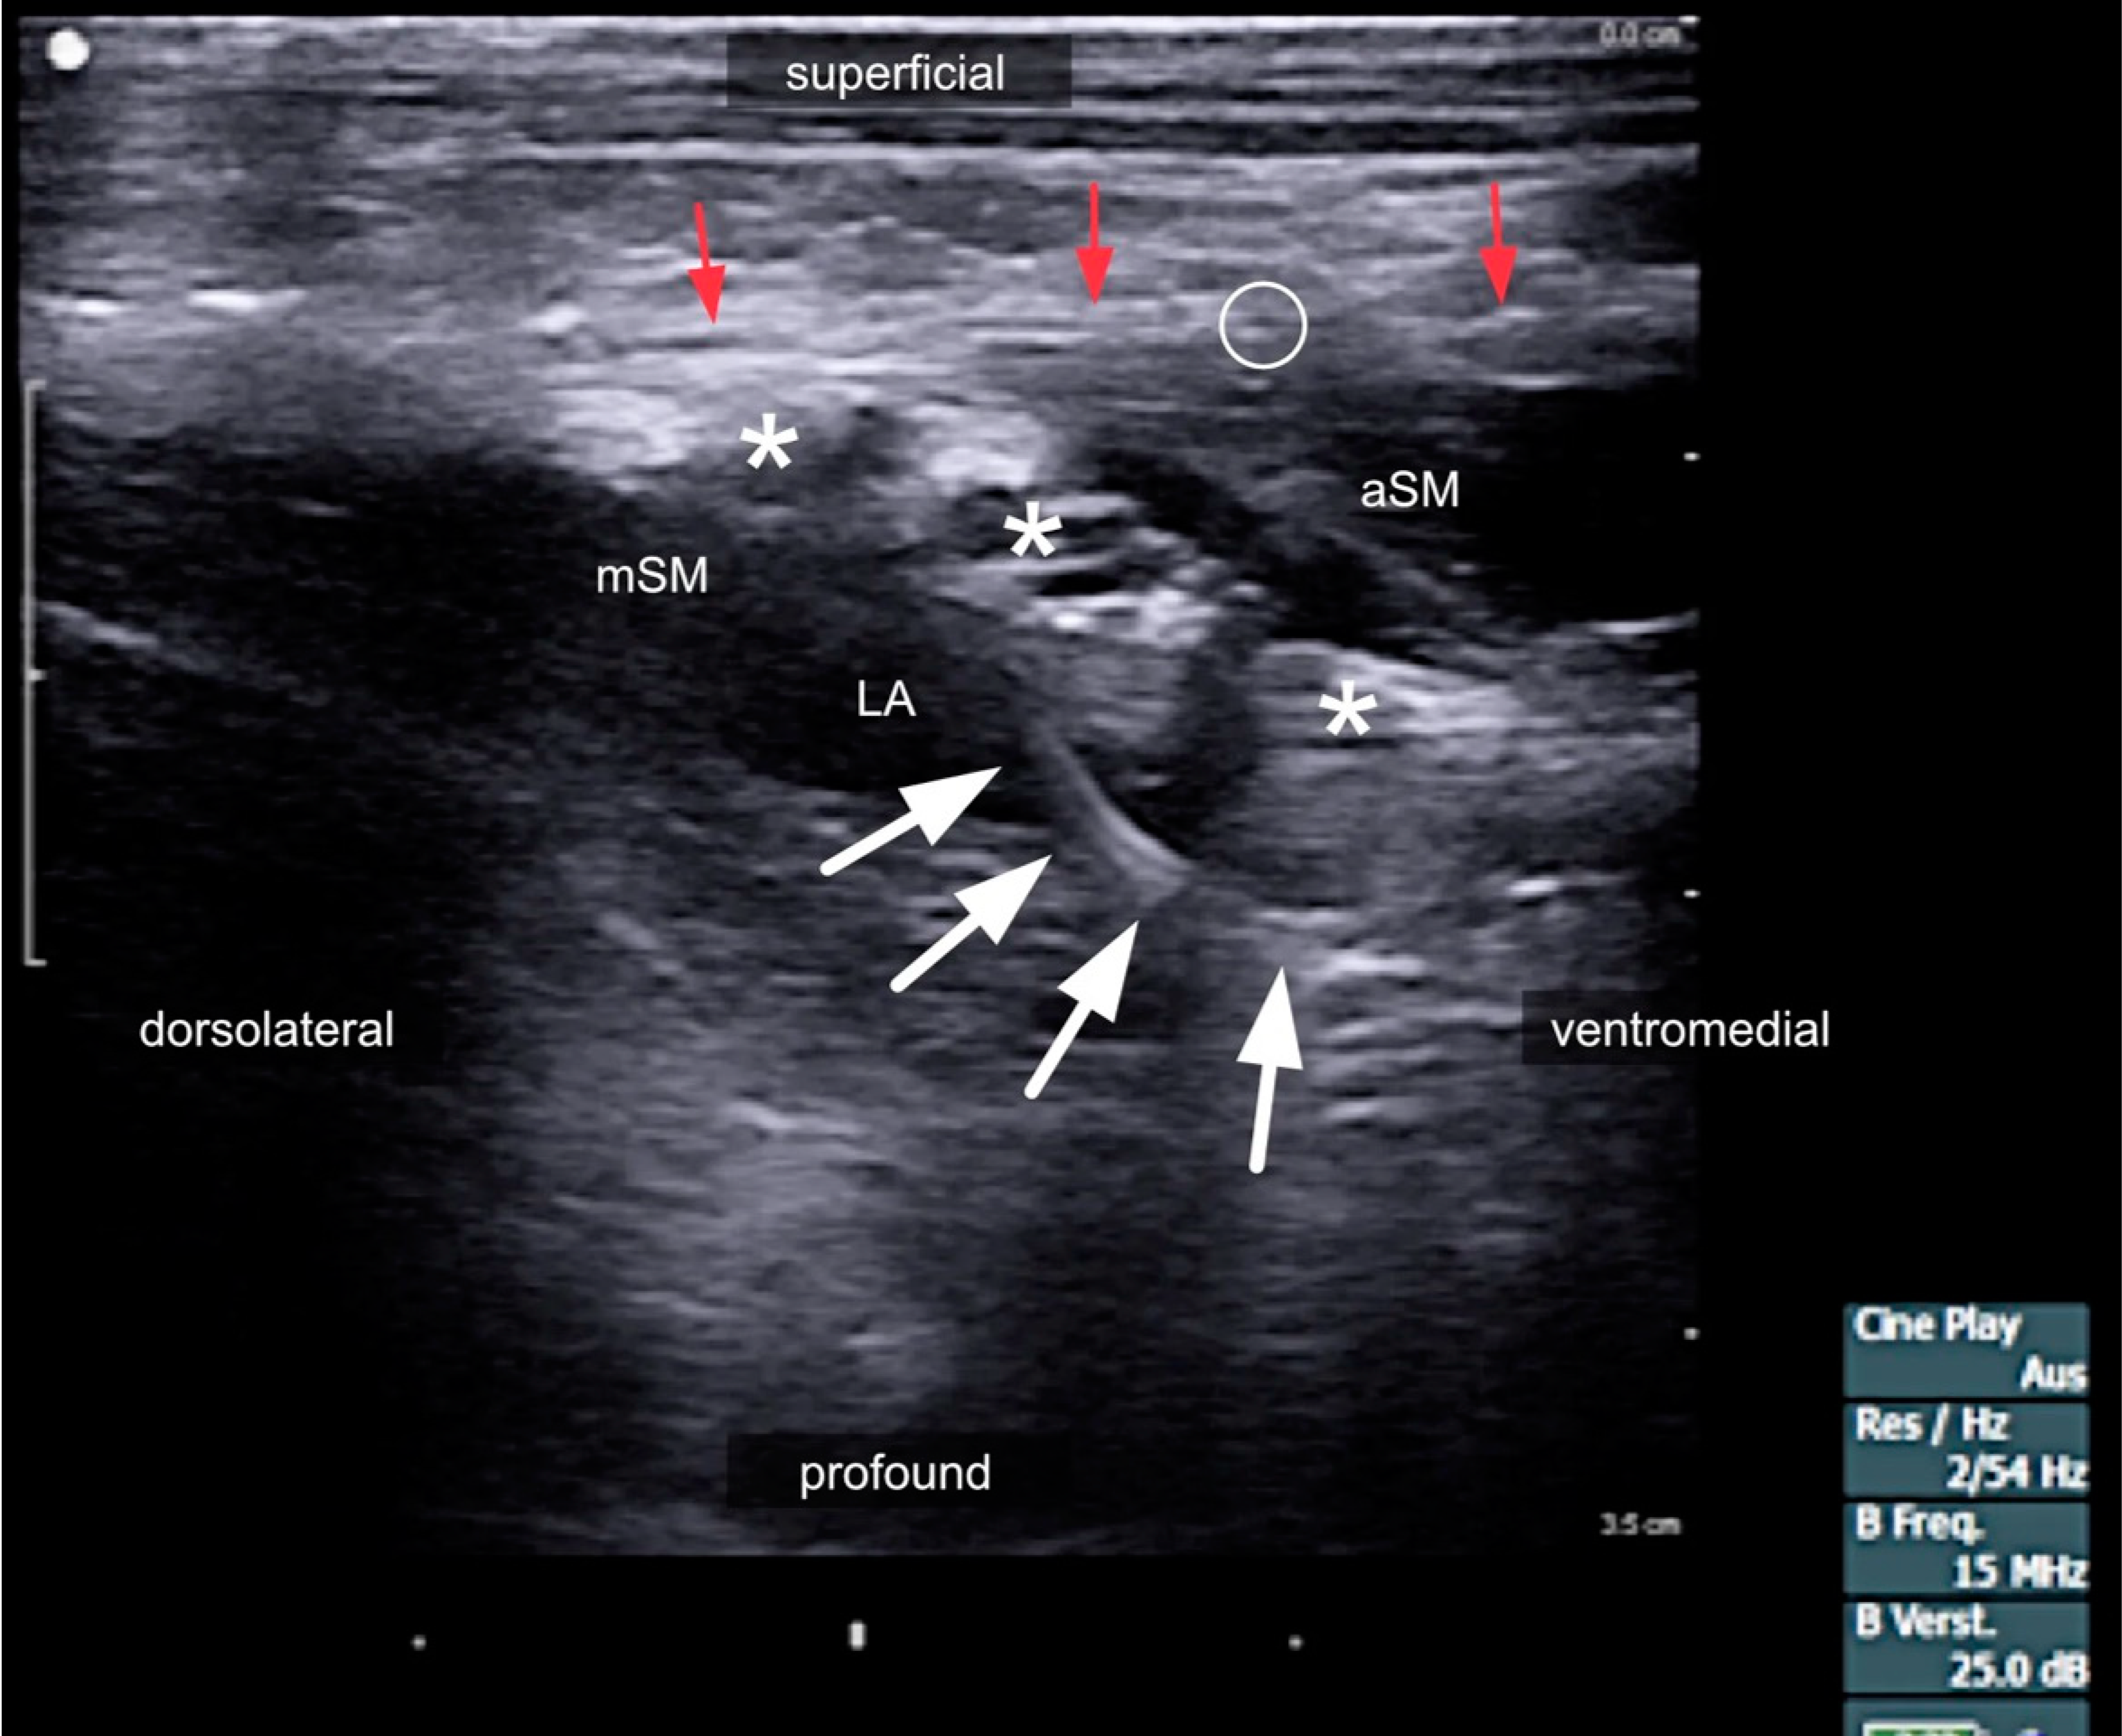

2.4. Compartments of the Lateral Neck and Their Relevance to Side Effects

2.5. Danger Space

3.3. The Risks of Interscalene Catheters